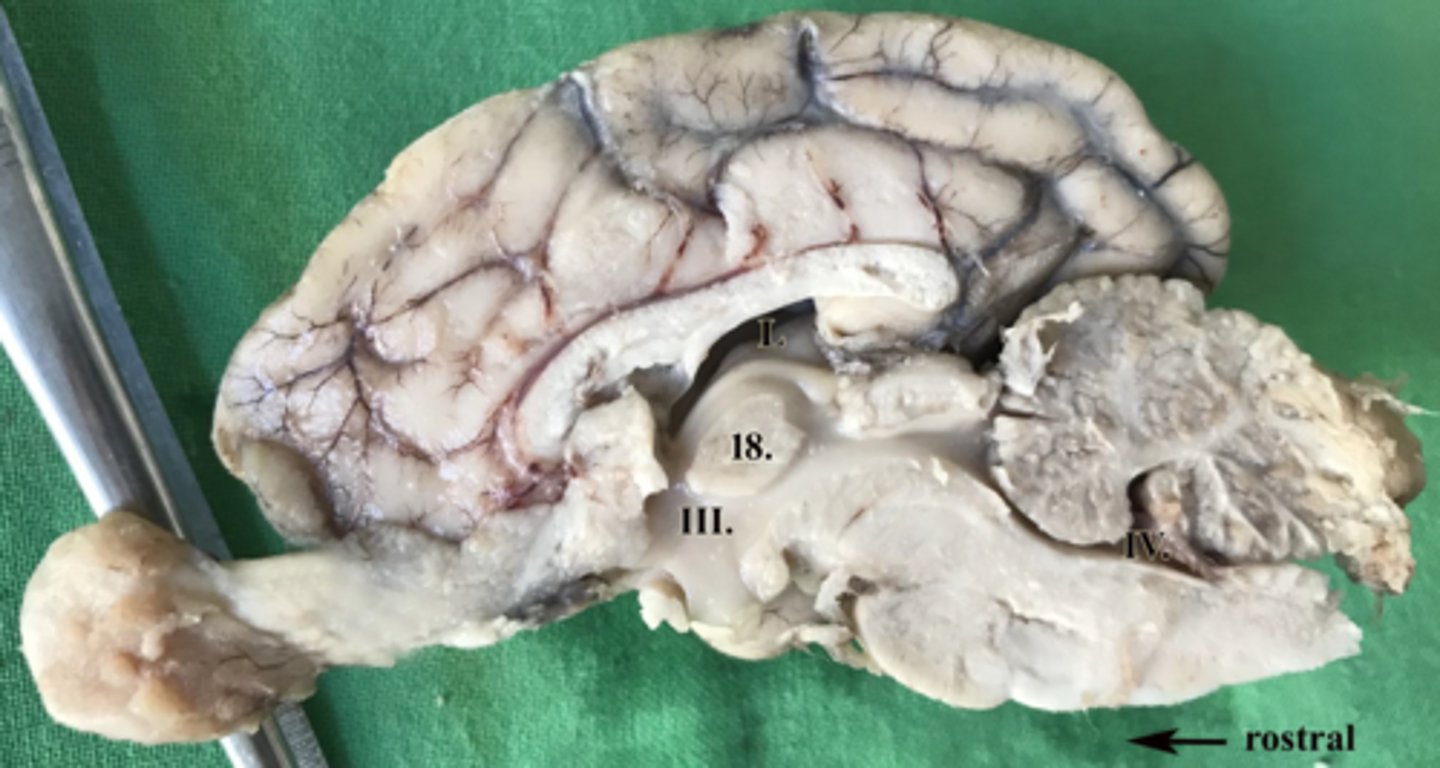

ventriculus tertius

III

ventriculus quartus

IV

ventriculus lateralis

L

adhesio interthalamica

18